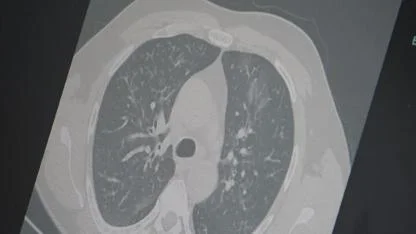

ABD'de ölümler 68 bini aştı

ABD'de Kovid-19 nedeniyle hayatını kaybedenlerin sayısı son 24 saatte 1142 artarak 68 bin 636’ya yükseldi.